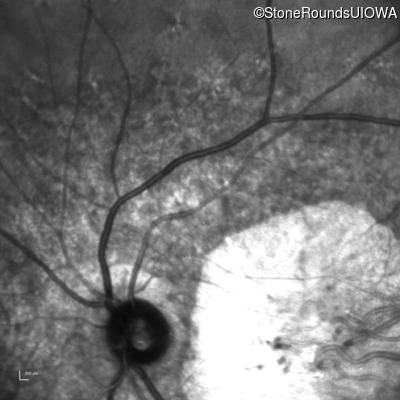

Infrared Fundus Photograph - Right - 20/160 +2 sc

Exemplar

Infrared Fundus Photograph - Left - 20/160 sc